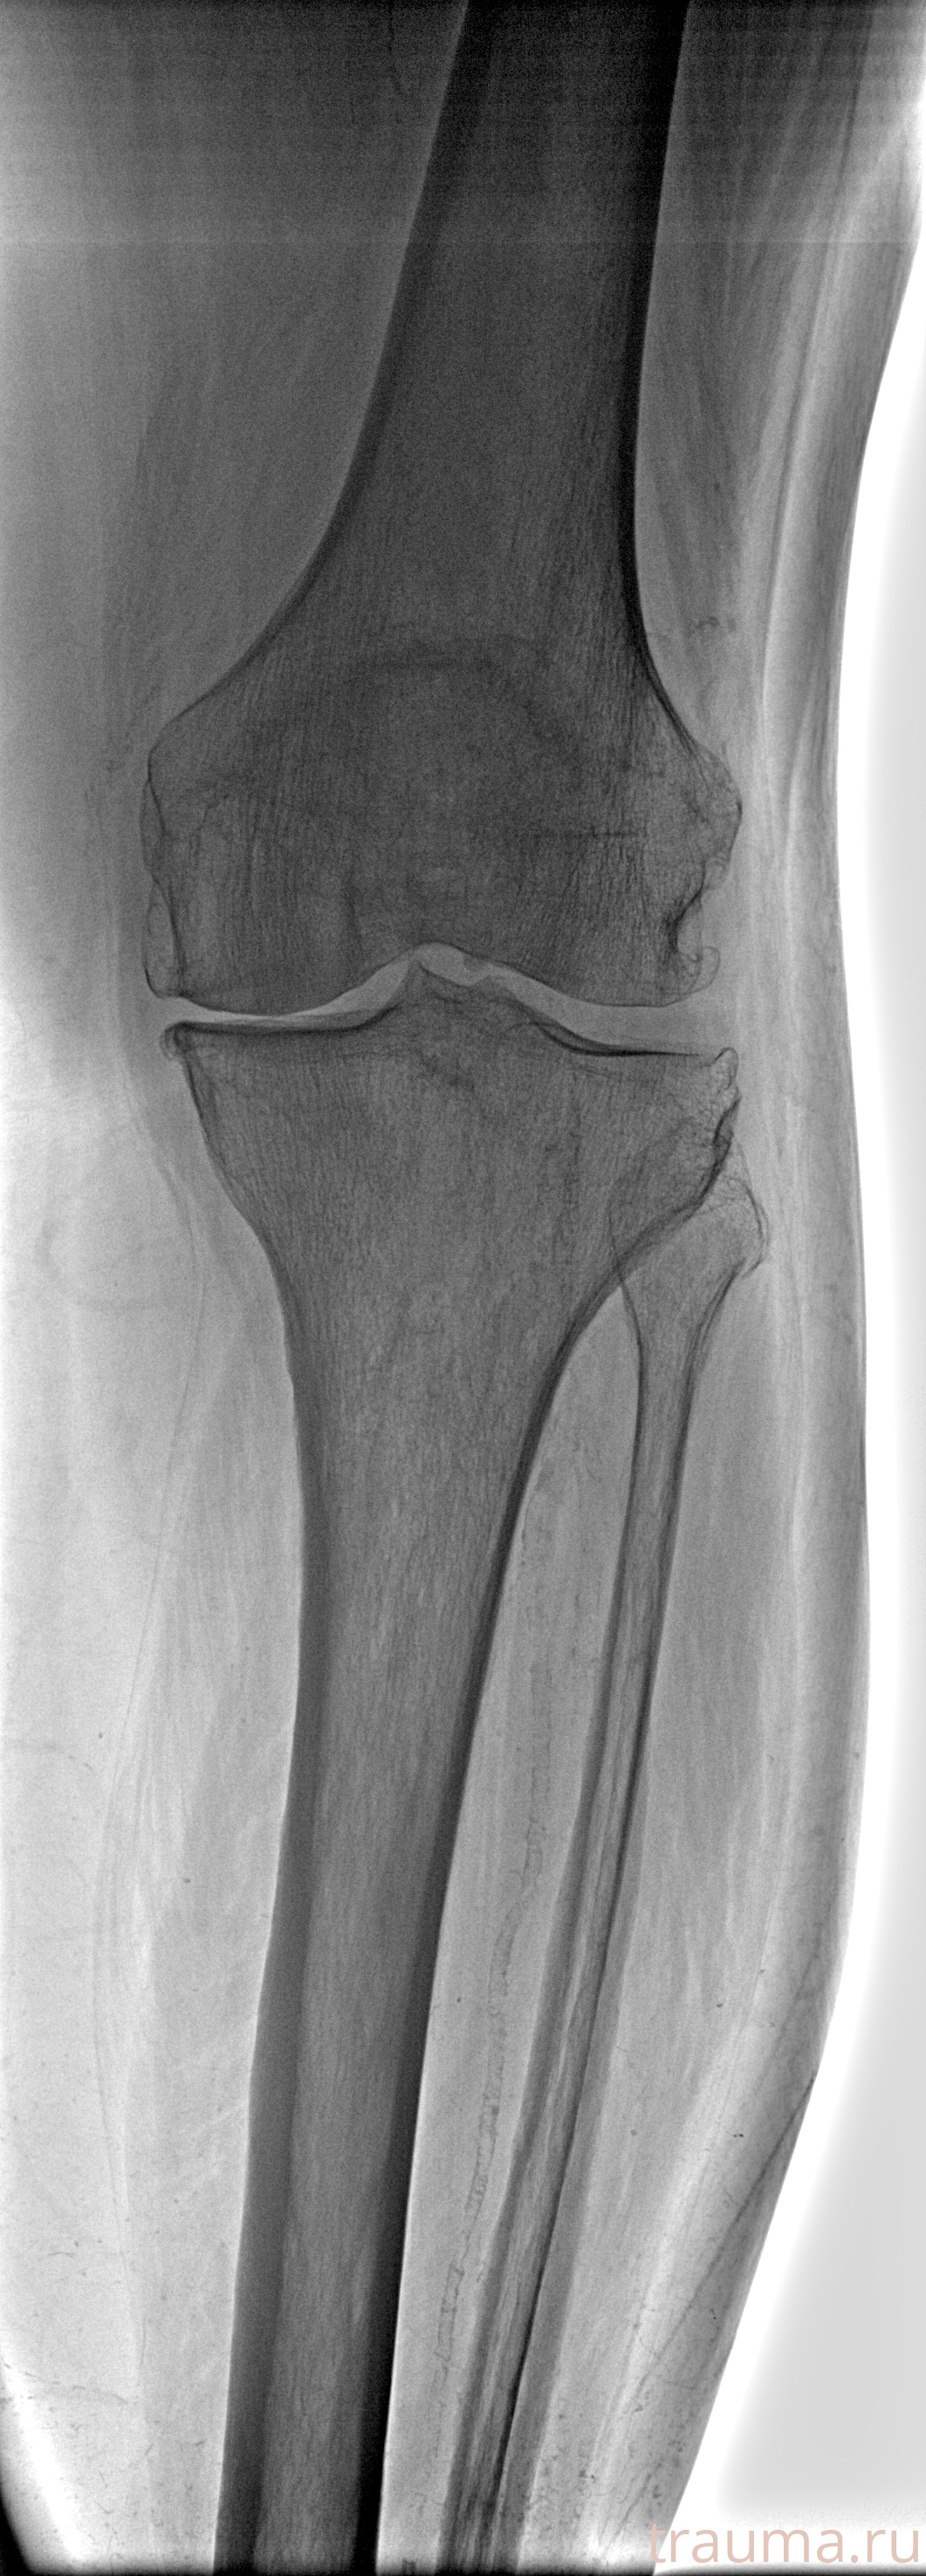

Рентгенограммы

Рентген на дому: по вашему адресу приезжает врач-рентгенолог, травматолог-ортопед с мобильным рентгеновским аппаратом, проводит диагностику травмы или заболевания, делает необходимые рентгенограммы, дает рекомендации по дальнейшему лечению. Получить качественные снимки в домашних условиях возможно благодаря уникальной методике, разработанной МосРентген Центром для института  Склифосовского